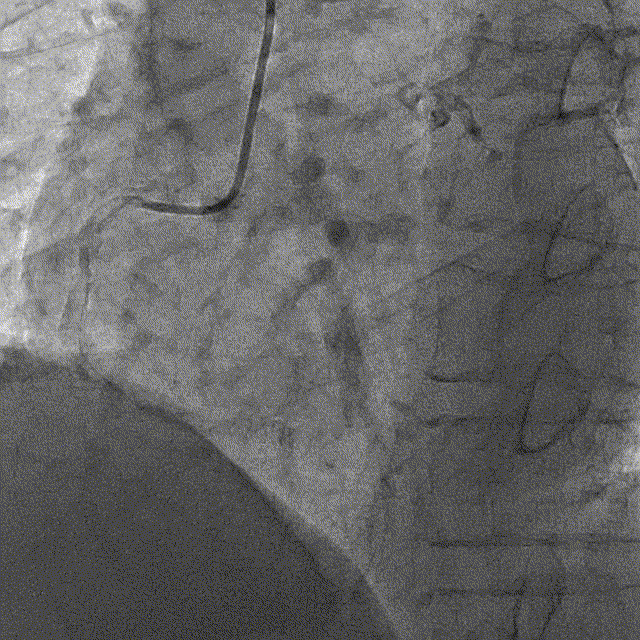

冠脉内介入治疗